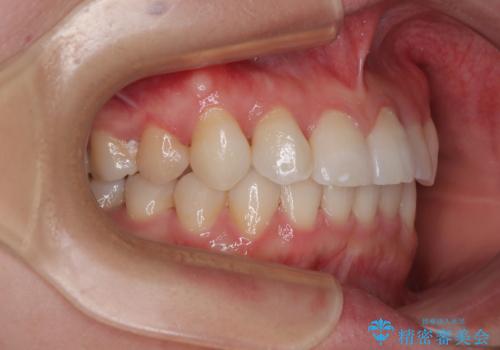

捻転の強い前歯 ワイヤー装置での非抜歯矯正

- 前歯のデコボコ、特に90度捻れている上顎前歯を気にして来院された患者様です。

当初予定通り1年半ほどの治療期間で、非常に綺麗な歯列に仕上げることができました。